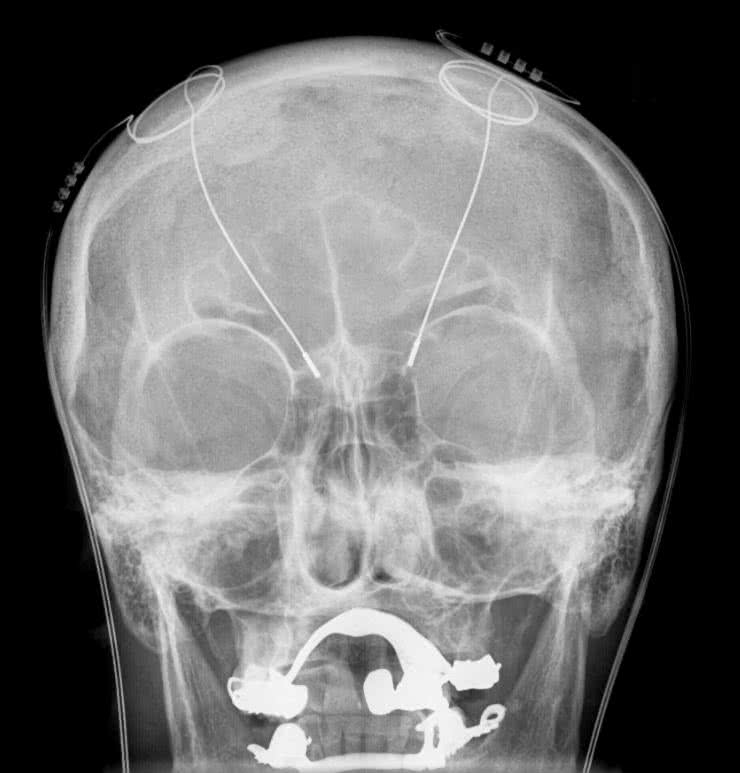

Jeśli instalowanie elektrod przy rdzeniu kręgowym wydaje się ryzykowne, to co powiedzieć o umieszczaniu ich wewnątrz mózgu? Głęboka stymulacja mózgu (DBS – Deep Brain Stimulation) stosowana jest w leczeniu szeregu schorzeń, począwszy od problemów ruchowych (choroba Parkinsona, dystonia, drżenie samoistne), neuropsychologicznych (np. zaburzenia obsesyjno-kompulsywne) czy neurologicznych jak padaczka. Fotografia 25 pokazuje zdjęcie rentgenowskie czaszki, na którym widać elektrody wewnątrz mózgu. Jak łatwo się domyślić, instalacja tych elektrod to proces skomplikowany i dość ryzykowny, dlatego metoda DBS stosowana jest tylko wtedy, gdy inne metody leczenia zawodzą.

Fotografia 25. Zdjęcie rentgenowskie ukazujące elektrody do głębokiej stymulacji mózgu. Źródło: Wikipedia.org